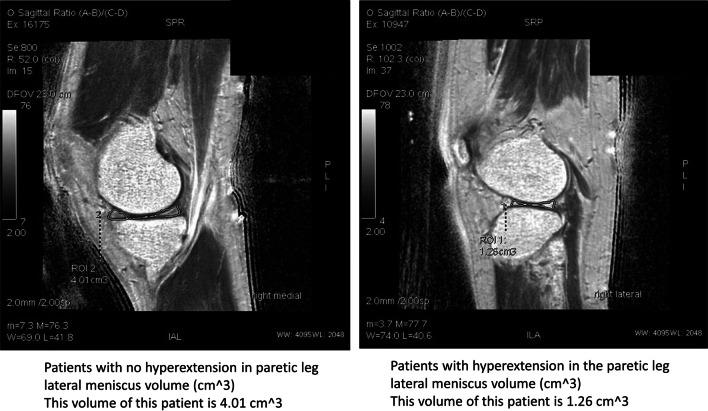

Fig. 4.

The meniscus volume between two stroke patients: no hyperextension in paretic leg (Left side) and had a hyperextension in paretic leg (Right side)

A moderate-to-strong correlation was found between the angle of knee hyperextension and the medial meniscus volume in non-paretic leg (R = − 0.53), between the angle of knee hypertension and the medial meniscus volume in paretic leg (R = − 0.57), and between the angle of knee hypertension and the lateral meniscus volume in paretic leg (R = − 0.70). More detail was shown in Figs. 3 and 4.